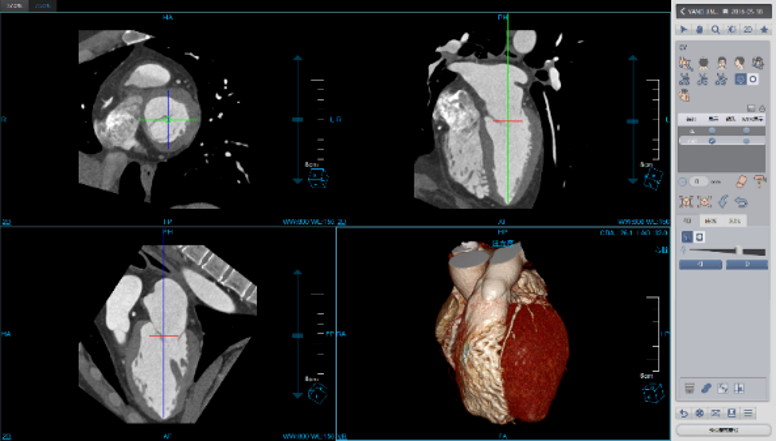

Cardiac Viewer Images

View heart images of each phase, execute three-dimensional reconstruction and heart extracted for CT heart images, and then view patient heart by more intuitive way, diagnosis various cardiovascular diseases.

• Different phases data comparison

• 4D play

• Oblique MPR display

Cardiac Function Analysis

Analyze a variety of heart functions

• Left ventricular volumes Ejection fraction

• Left ventricle wall motion and thickening

• 4D Rendering

One Station Cardiac Diagnosis Analysis